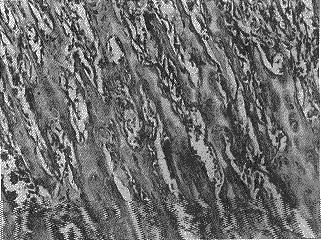

二、骨组织病理切片

去势组大鼠骨组织病理切片显示骨小梁稀疏、断裂、骨髓腔扩大,提示骨质疏松形成。(见封二图4)。而去势后予倍美力组大鼠骨组织病理切片均示骨小梁排列整齐,骨髓腔大小正常,(见封二图5)。

图(四)去势组大鼠的骨组织切片HE染色10×10

图(五)ERT组大鼠的骨组织切片HE染色10×10

图(六)正常对照组大鼠的骨组织切片HE染色10×10